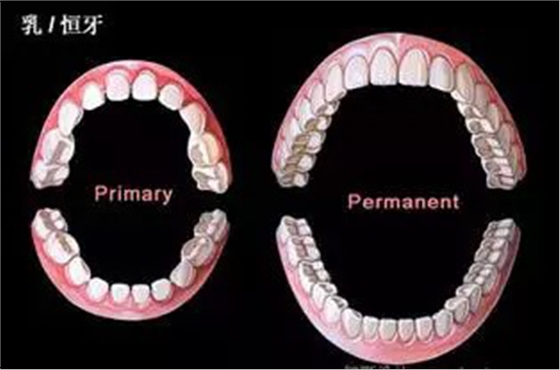

正畸

錯(cuò)合畸形高發(fā)時(shí)間:

乳牙列和恒牙列早期

QQ圖片20150711104419.png

瑞典一項(xiàng)縱向觀察研究顯示,處于乳牙列和恒牙列早期的兒童錯(cuò)合畸形的發(fā)病率高,亟需正畸治療;在乳牙列向早期恒牙列轉(zhuǎn)換的過(guò)程中,存在大量自我矯正和新的錯(cuò)合畸形的發(fā)生。該論文于2015年4月13日在線發(fā)表于《安格爾正畸醫(yī)師》(Angle Orthod)雜志。

研究人員對(duì)277名納入兒童分別在其3歲、7歲和11.5歲進(jìn)行隨訪,通過(guò)臨床檢查確定其是否患有錯(cuò)合畸形和需要正畸治療,通過(guò)問(wèn)卷調(diào)查和口腔檢查搜集患兒允指習(xí)慣、呼吸紊亂、過(guò)敏、口腔頜面外傷以及正畸治療的情況。

結(jié)果為,3歲兒童的錯(cuò)合畸形發(fā)病率為71%,7歲時(shí)為56%,11.5歲時(shí)為71%;前牙開(kāi)合、矢狀面方向的錯(cuò)合、后牙反合可在一定程度上出現(xiàn)自我矯正,但深覆合會(huì)繼續(xù)加重;大量咬合接觸點(diǎn)的變化和牙間隙的出現(xiàn),導(dǎo)致11.5歲時(shí)錯(cuò)合發(fā)病率高達(dá)71%;22%的患者亟需正畸治療;患兒3歲時(shí)的口腔不良習(xí)慣、過(guò)敏以及呼吸紊亂與其11.5歲時(shí)的錯(cuò)合畸形并無(wú)明顯關(guān)聯(lián)。(陸慧 編譯)